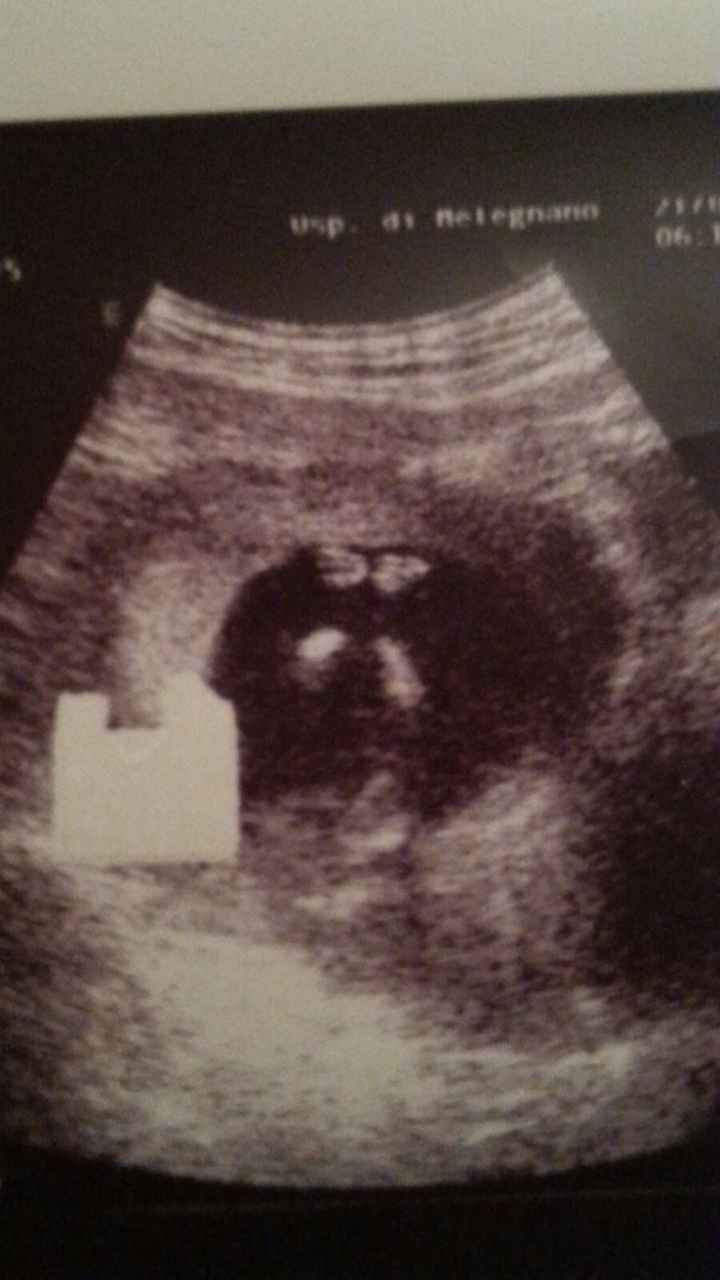

Melegnano, Milano · Da Febbraio 2015